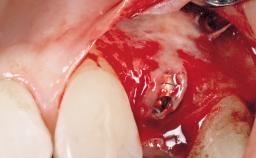

Late Placement of an Implant in a Maxillary Left Central Incisor Site

A 36-year-old female patient was referred for the replacement of the upper left central incisor (tooth 21), which had fractured. Although the tooth had been asymptomatic for many years, the crown began to loosen, at which time she presented to her dentist for an assessment. Teeth 21 and 22 had both been endodontically treated many years previously. She was a healthy individual and a non-smoker.

The crown of tooth 21 was splinted to the adjacent teeth with composite resin, and the gingiva was inflamed.